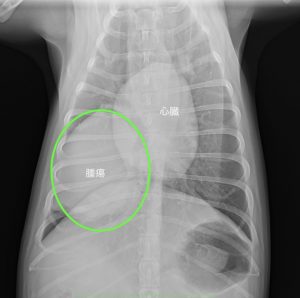

今回ご紹介するわんちゃんは咳が出るようになりかかりつけ動物病院を受診したところレントゲン検査で右肺後葉に大きな腫瘍が見つかり、当院を紹介来院しました。

より詳しい診断のためCT検査を行いました。

腫瘍は心臓よりも大きく、右肺後葉に発生していました。

他の肺に転移は認められずリンパ節への転移もありませんでした。